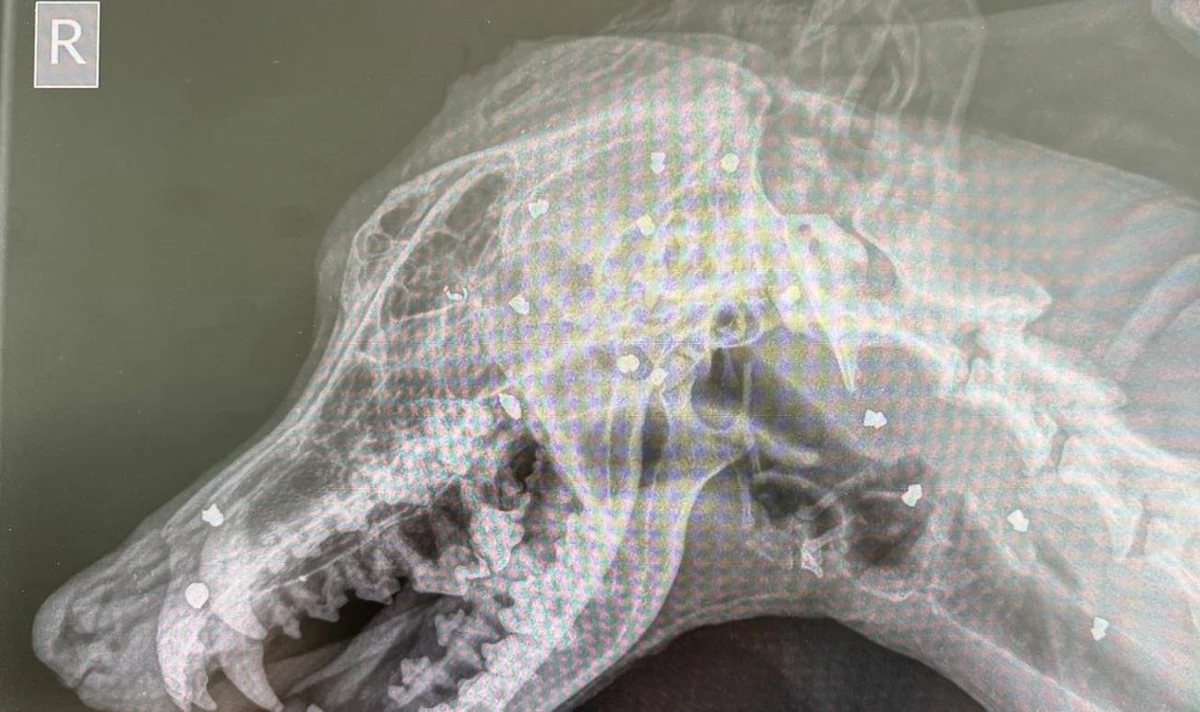

W schronisku przeprowadzono szczegółowe badania. Zdjęcie rentgenowskie ujawniło przerażającą prawdę: w głowie psa znajdowały się aż 42 śruty diabolo używane w wiatrówkach. Część z nich była głęboko wbita w kości i mięśnie, co czyniło operację wyjątkowo skomplikowaną i ryzykowną. Mimo ogromnych trudności lekarzom udało się przeprowadzić trzy zabiegi, podczas których usunięto znaczną liczbę pocisków. Niestety, niektóre z nich pozostały - są zbyt blisko ważnych naczyń krwionośnych lub wręcz zrosły się z kośćmi, przez co ich usunięcie mogłoby zagrozić życiu zwierzęcia.